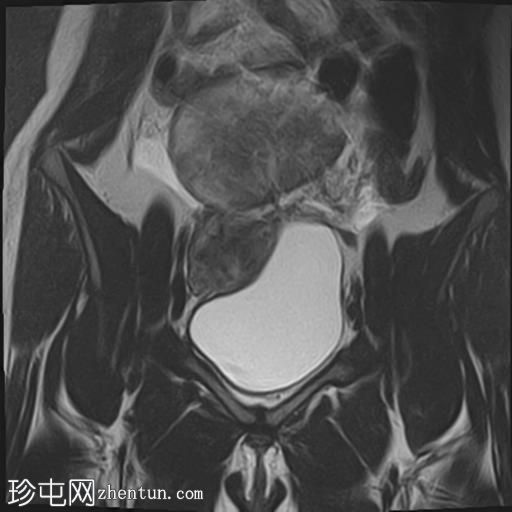

冠状位

T2加权像

盆腔内可见多个边界清晰的肿块:

其中一个位于子宫上方,T2加权像呈中等信号,中心区域呈高信号,增强T1脂肪抑制像未见强化。右侧卵巢增大,增厚的血管蒂扭曲,未见强化,轴位和矢状位T2加权像均显示清晰。

另一个位于子宫后窝,T2加权像呈中等信号,增强扫描显示明显强化。

轻度腹腔积液